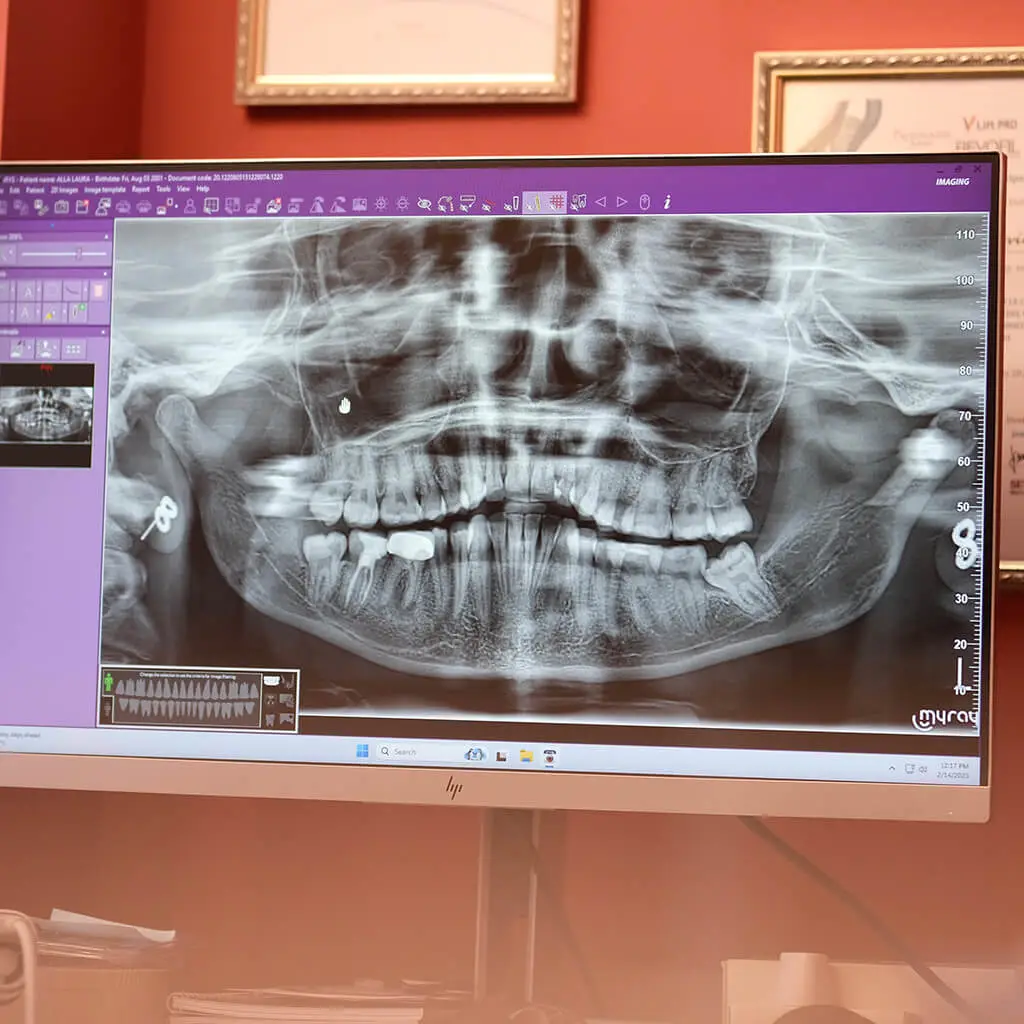

• Analisi TAC 3D e visita preliminare

• Studio del caso clinico e del volume osseo

• Scelta del numero e del tipo di impianti